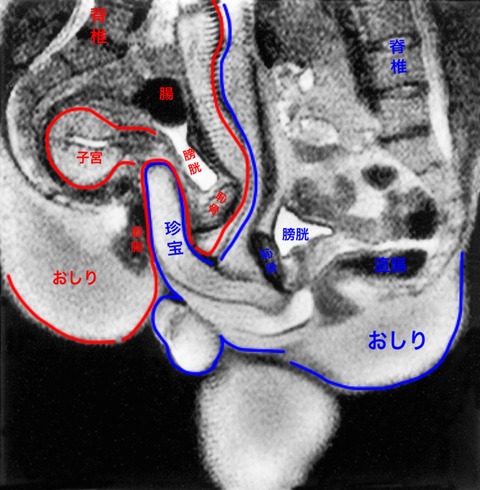

珍宝

俺のちんぽじゃ到底子宮に届かないんだけど?

>>4

ちんぽじゃねぇ珍宝だ

ちんぽじゃねぇ珍宝だ